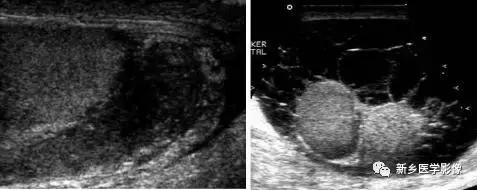

超声:*丸睾**、附睾不同程度肿大,包膜尚清楚,实质回声增粗、不均匀。出现脓肿时可见低回声肿块呈蜂窝状,边界欠清晰。多数伴有鞘膜积液。部分病例精索增粗,阴囊壁增厚。

CDFI示:*丸睾**、附睾内血流信号明显增多有的*丸睾**血流呈“彩球状”。出现脓肿时血流不丰富,PW:流速加快,阻力降低。

*丸睾**、附睾不规则增大,边界欠清晰,内部回声不均,可见钙化强回声,附睾尾部易形成病灶。脓肿形成时,可见细点样回声。脓肿破向鞘膜腔时,于腔内可见大量细点样回声的液体,破向阴囊壁时,可见阴囊壁增厚、回声不均及无回声区。病灶可局限于附睾尾部,呈低或稍高回声,境界尚清晰。

CDFI示:局限性小病灶血供不丰富,多发病灶、大病灶,血供常增多,血流速度可加快。